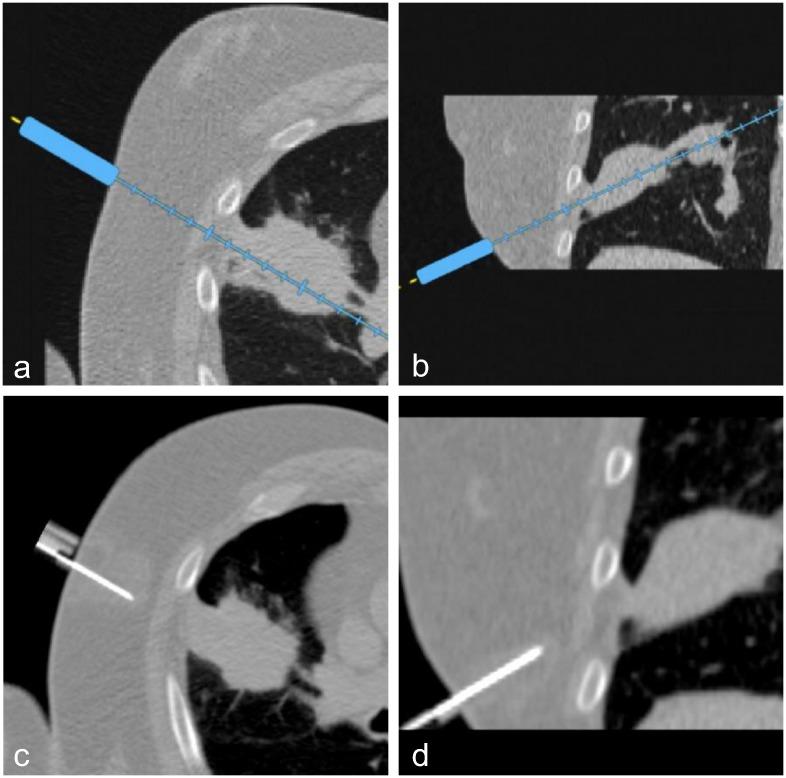

120 patients requiring a percutaneous CT intervention (drainage, biopsy, tumor ablation, infiltration, sympathicolysis) were included in this prospective randomized trial. Nineteen radiologists participated. Conventional procedures (CT group) were compared with procedures assisted by a navigation system prototype using an electromagnetic localizer to track the position and orientation of a needle holder (NAV group). The navigation system displays the needle path in real-time on 2D reconstructed CT images extracted from the 3D CT volume. The regional ethics committee approved this study and all patients gave written informed consent. The main outcome was the distance between the planned trajectory and the achieved needle trajectory calculated from the initial needle placement.

120例需要进行经皮CT介入(引流、活检、肿瘤消融、浸润、交感神经溶解)的患者纳入了这项前瞻性随机试验。19名放射科医生参与其中。将传统操作(CT组)与使用电磁定位器跟踪持针器位置和方向的导航系统原型辅助操作(导航组)进行比较。该导航系统在从3D CT容积中提取的2D重建CT图像上实时显示针道。地区伦理委员会批准了本研究,所有患者均签署了书面知情同意书。主要结果是根据最初的针放置计算出的计划轨迹与实际针轨迹之间的距离。